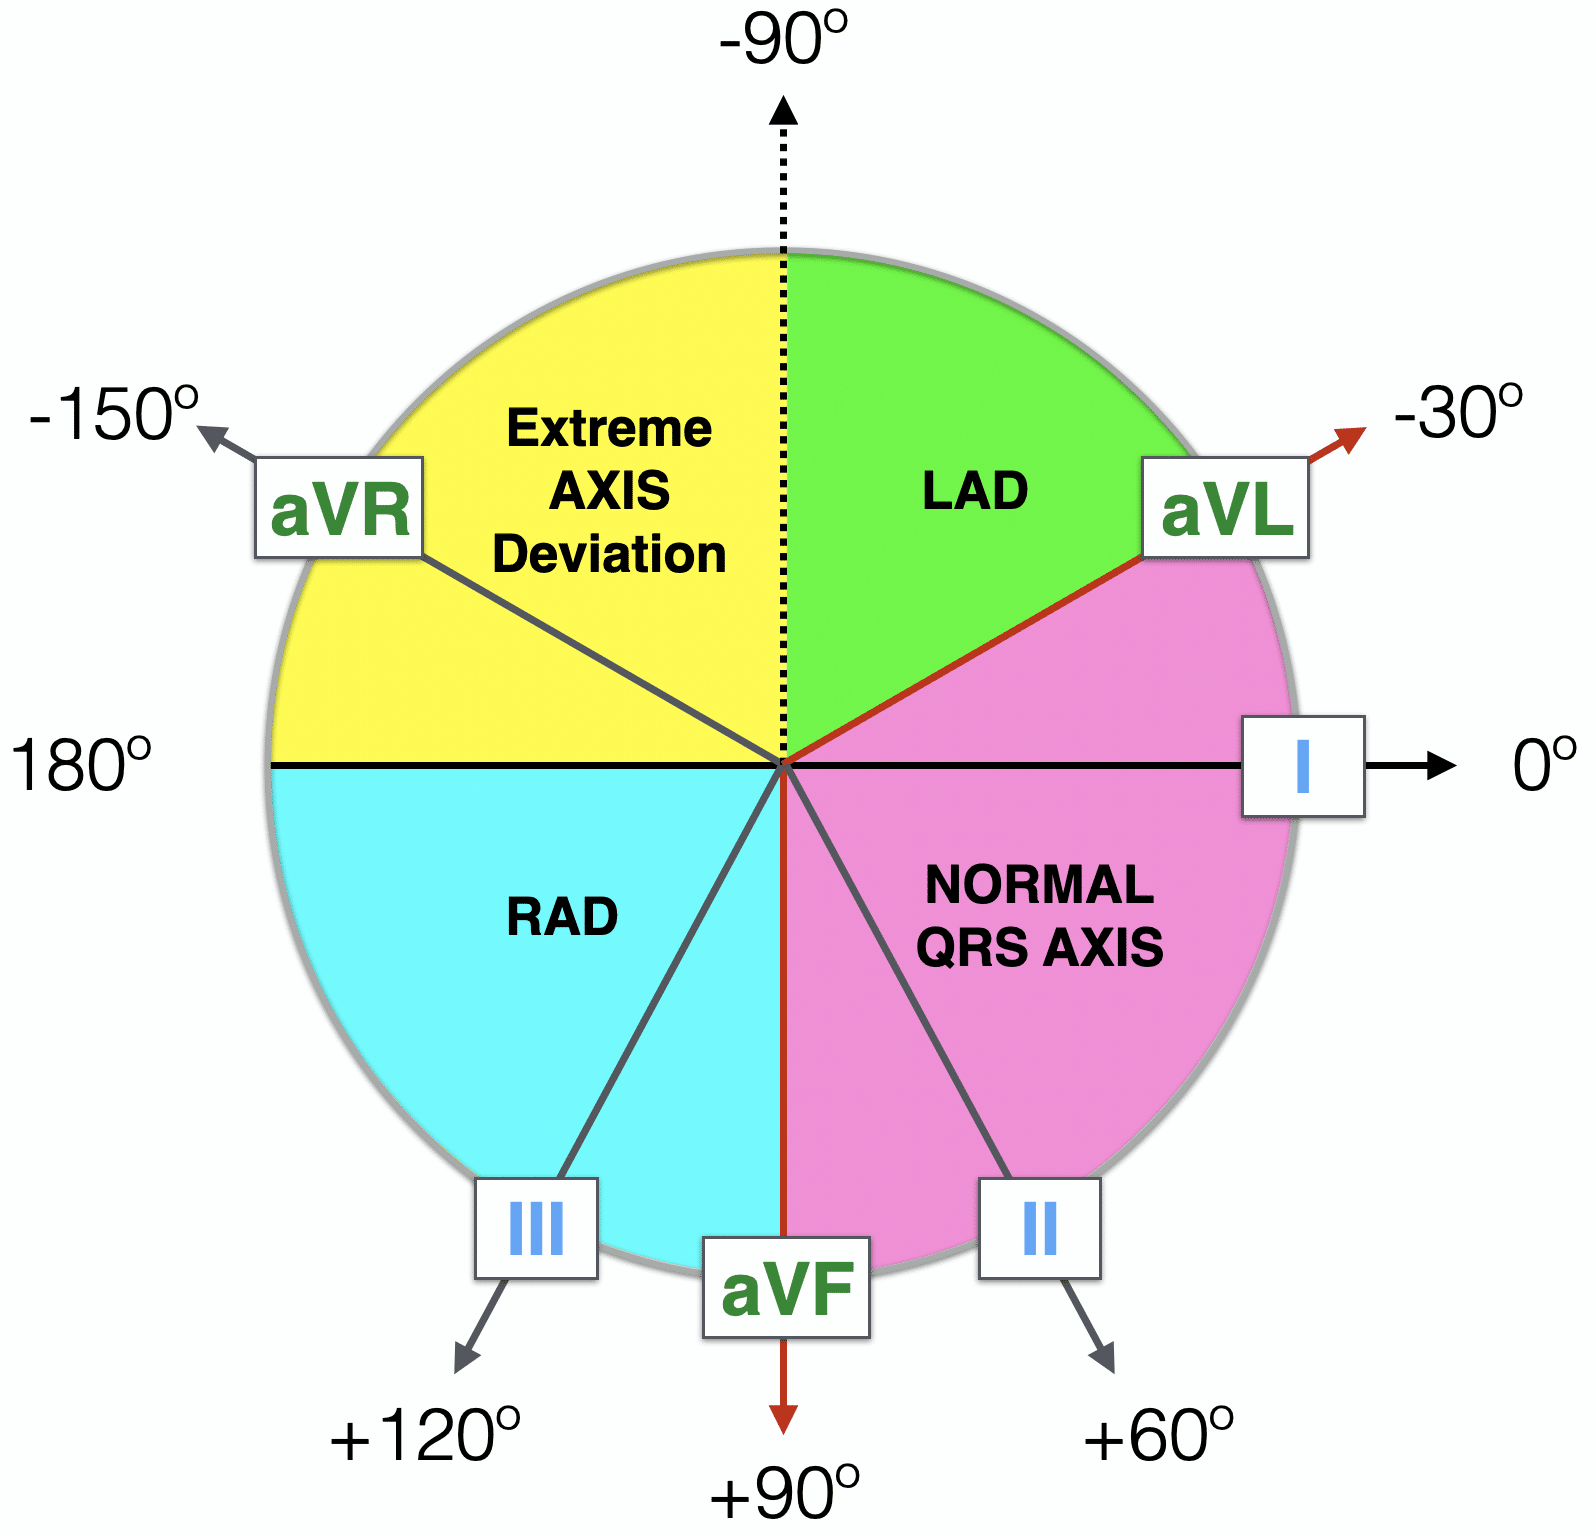

4. Axis

The cardiac axis describes the overall direction of ventricular depolarisation

- In simple terms, it tells you which way the electrical current in the heart is predominantly moving

Normal axis and axis deviations:

| Type of Axis | Angle Range (°) |

|---|---|

| Normal axis | −30° to +90° |

| Left axis deviation (LAD) | −30° to −90° |

| Right axis deviation (RAD) | +90° to +180° |

| Extreme (north-west) axis deviation | −90° to ±180° |

In practice, most modern ECG machines automatically calculate the cardiac axis. While determining the exact numerical angle requires trigonometric calculation, this is not expected in exams or clinical practice.

Instead, clinicians are generally expected to recognise whether the axis is normal or deviated, which can be quickly done using the “Thumbs Rule” described below:

-

👍 Lead I up (+ve), 👍 aVF up (+ve) → normal axis

-

👍 Lead I up (+ve), 👎 aVF down (-ve) → left axis deviation (thumbs/leads ‘Leaving’ each other → Left axis deviation)

-

👎 Lead I down (-ve), 👍 aVF up (+ve) → right axis deviation (thumbs/leads ‘Reaching’ each other → Reft axis deviation)

- 👎 Lead I down (-ve), 👎 aVF down (-ve) → extreme (north-west) axis deviation

The 4-quadrant helps visualise the axis deviation and how it corresponds with the limb leads.

https://litfl.com/ecg-axis-interpretation/

© Life in the Fast Lane. Licensed under CC BY-NC 4.0